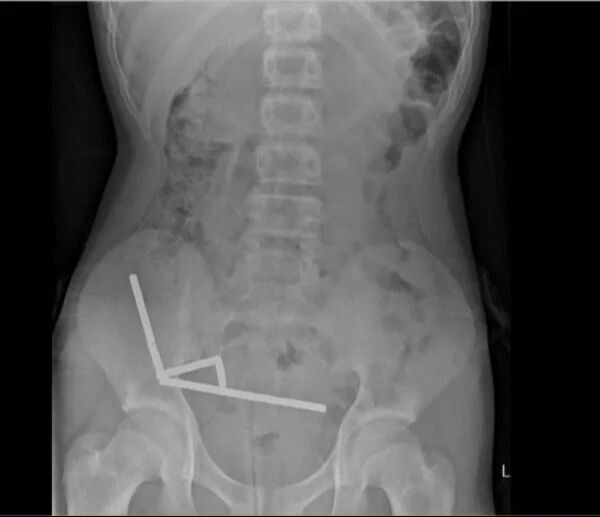

Röntgen görüntülerinde, çocuğun bağırsaklarında zincir halinde dizilmiş metal toplar tespit edildi. Ameliyatta bu mıknatısların ince bağırsak ve çekumda birbirine yapışarak kan akışını kestiği ve “basınç nekrozu” denilen doku ölümüne yol açtığı ortaya çıktı.